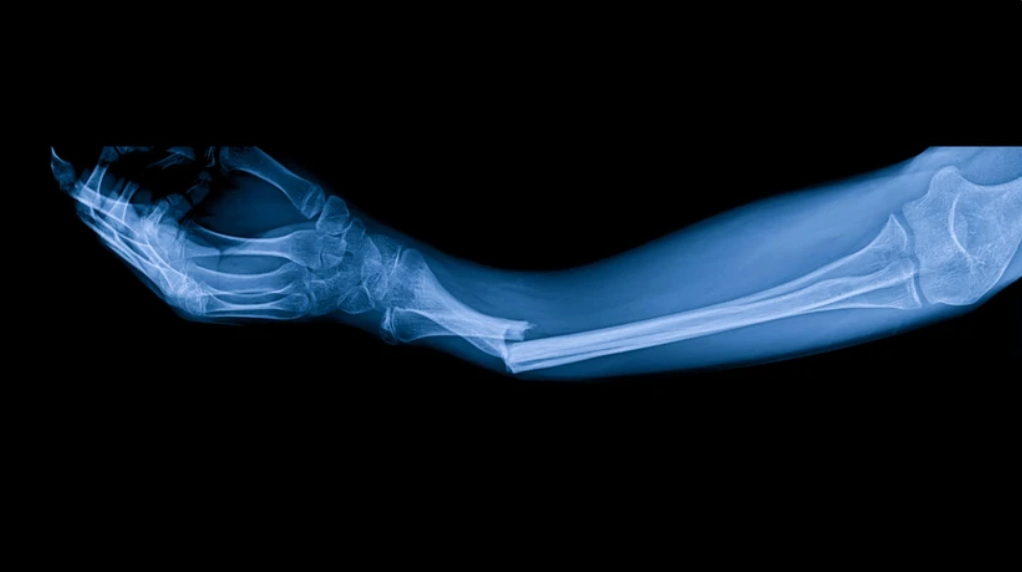

En ocasiones, la naturaleza es la mejor maestra de la ciencia. Los organismos vivos han desarrollado soluciones a problemas complejos durante millones de años de evolución, y los científicos, observadores atentos, han aprendido a traducir esas estrategias biológicas en innovaciones médicas. El más reciente ejemplo proviene de China, donde un grupo de investigadores ha logrado desarrollar un “pegamento óseo” capaz de reparar fracturas en apenas tres minutos, inspirado en el mecanismo con el que las ostras se adhieren con firmeza a las superficies rocosas en el mar.

Actualmente, el tratamiento de una fractura requiere un proceso prolongado: reducción de la fractura, inmovilización mediante yeso, clavos, placas o tornillos, y un largo periodo de recuperación que puede extenderse de semanas a meses. En casos graves, como fracturas múltiples o en huesos de carga (fémur, tibia), la cirugía suele ser invasiva y la rehabilitación, dolorosa.

El pegamento óseo propuesto por el equipo chino ofrece un cambio radical: al aplicarse sobre el área de la fractura, sella y fija el hueso en apenas tres minutos. Esta rapidez no solo acelera la recuperación, sino que reduce el riesgo de infecciones, elimina la necesidad de implantes metálicos y minimiza la estancia hospitalaria.